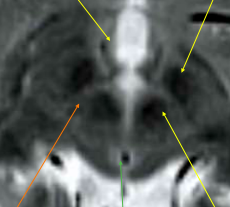

8

Q

Label A-C

A

A: PAG

B: substantia nigra

C: red nucleus